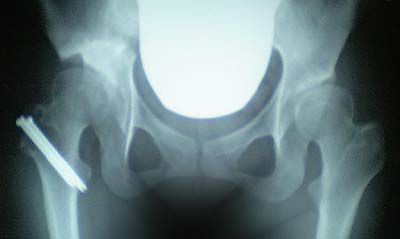

■いくらスペシャルヌード画像(レントゲン

の写真とも言う)

またデジカメ忘れて携帯で撮影。

骨に埋まっているボルト2本を抜く手術が必要で来月に予約をいれました。

ボルトを抜いたほうが筋トレがスムーズにいくんだとか。

すごいはっきりボルトが見える~!!ヽ(・_・;)ノ